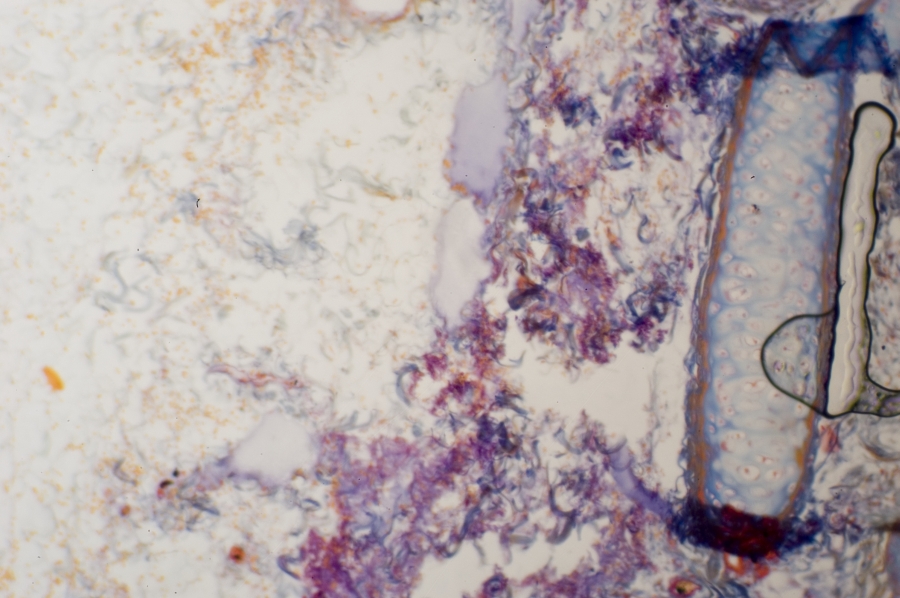

Image Filename: 36931_4495-2

36931_4495-2

container invno 36931

specimen id 4495